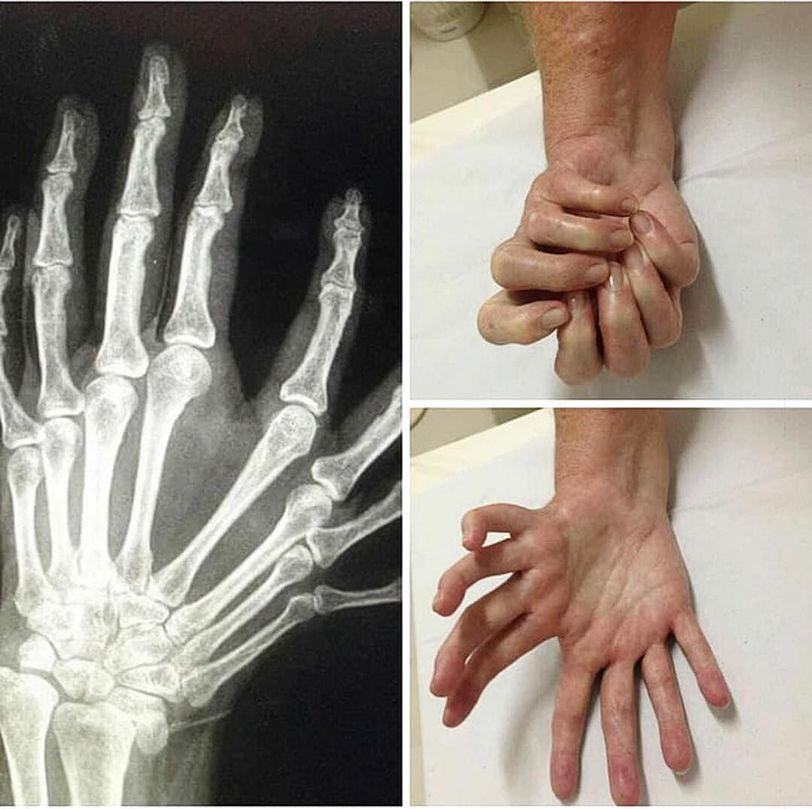

Ulnar dimelia or mirror hand syndrome is a rare congenital anomaly of the upper limb characterized by absence of radius, duplication of ulna and symmetric polydactyly (seven or eight fingers and lack of thumb). Less than 100 cases have been reported in the literature till today.

Do all of the fingers function normally? Can the patient use each and every finger individually? Does the other hand have 5 digits?